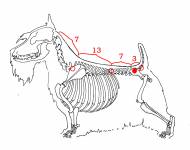

páteř psa a možné lokalizace přechodového obratle

páteř psa a možné lokalizace přechodového obratle